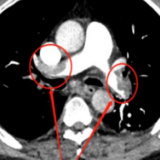

事不宜迟,许爹爹经绿色通道被快速送入放射影像科行肺动脉CTA检查。结果发现,老人的肺动脉有多处栓塞(左、右侧肺动脉、双侧肺动脉各段主干及部分亚段均有栓塞);超声检查发现他的双下肢静脉有明显血栓形成,心脏彩超提示右心增大,说明肺栓塞已累及心脏,许爹爹随时有性命之忧!